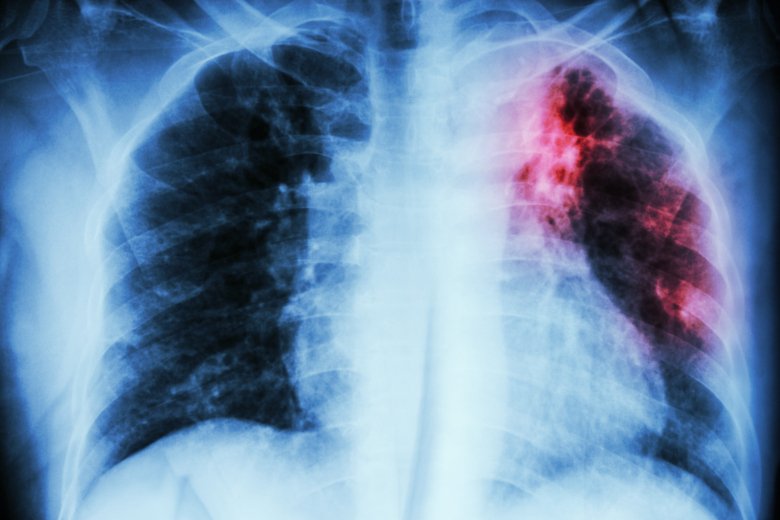

Photo: Gettyimages.RESTAKE: Health system and community resilience during Covid-19 through the example of tuberculosis

Photo: Gettyimages.Utility of aerosol-based detection of Mycobacterium tuberculosis in predicting household transmission

Photo: Gettyimages.Migrant TB screening in Sweden

Photo: Gettyimages.Artificial Intelligence-Assisted Tuberculosis Screening in Viet Nam

Photo: Unknown KIArtificial intelligence for diagnostics of cancer and infectious diseases in resource-limited settings - the MoMic Project